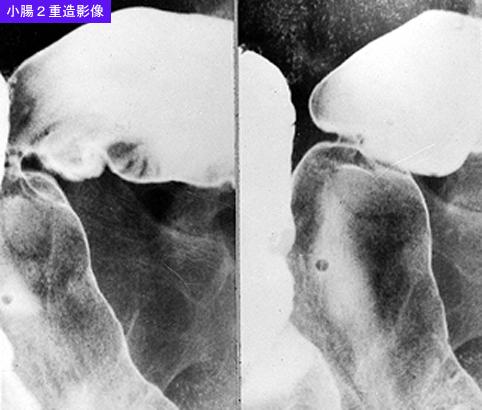

疾患(病理主体)の分類炎症性・潰瘍性疾患/結核

部位(臓器別)小腸/回腸

検査方法X-P